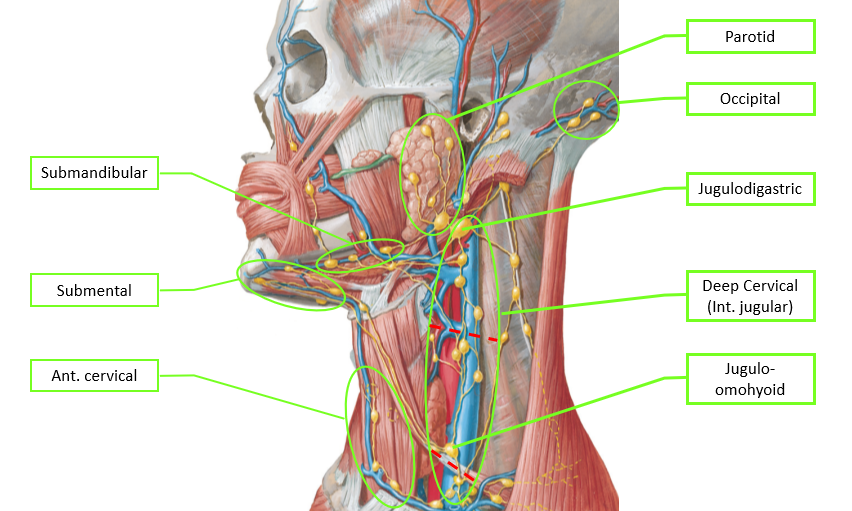

Lymphatic system

總圖

Nodes

Lingual Lymphatic nodes

病灶

Groups

- Level I

- the submental group (Ia), and the

submandibular group (Ib). - Level II

- the upper jugular lymph nodes

- level IIa – CN XI 前

- level IIb – CN XI 後

- Level III

- the middle jugular lymph nodes

- Level IV

- the lower jugular lymph nodes

- Level V

- all lymph nodes contained within the posterior triangle

- Level VI

- lymph nodes of the anterior (central) neck compartment

Tip

清除 I, II, III

Nasal cavity

Oral cavity

Tongue

Tonsil

Waldeyer’s tonsillar ring

Face

- Maxillary

- Buccinator

- Supramadibular

Larynx

用vocal fold 分,上,下分別到SDC, IDC

Thyroid

跟著Sup./ Inf. thyroid a.走,分別到SDC, IDC

Nose